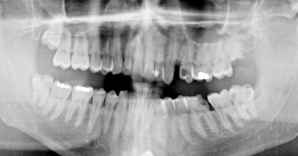

Zur Diagnostik sollte ein

sogenanntes Orthophantomogramm - das ist eine Aufnahme von beiden Kiefern -

erstellt werden. An Hand dessen kann eine Übersichtsdiagnose und bei Zweifel

durch eine oder mehrere Einzelaufnahmen eine genaue Diagnose gestellt werden.

Diese Aufnahmen sollten nicht älter als 1-2 Monate sein und mitgenommen werden.

Auf

dem Röntgenbild sehen wir vier verlagerte Weißheitszähne, die auf Grund ihrer Lage als Problemfälle anzusehen sind. Speziell der obere linke Weißheitszahn

ist schon kariös sehr zerstört. In diesem Fall ist vor einer Langfahrt eine operative Entfernung sämtlicher Weißheitszähne durchzuführen.